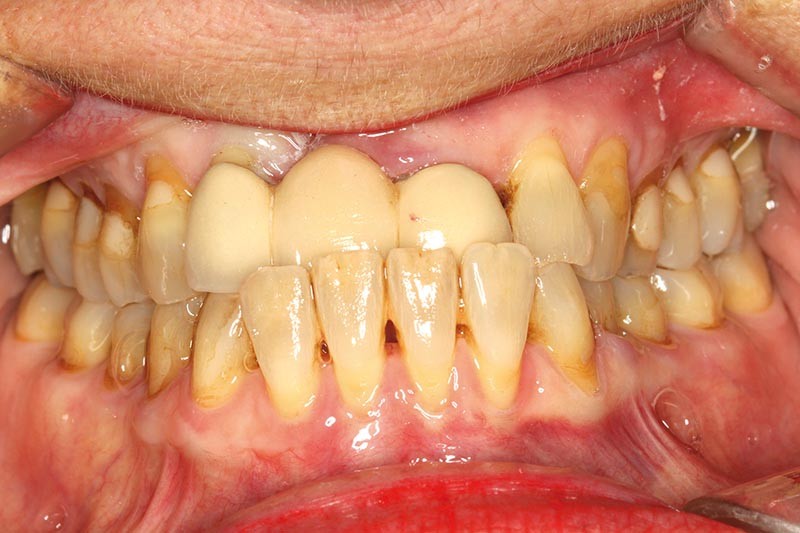

Une patiente présente un proglissement mandibulaire aboutissant à une inversion d’occlusion au niveau des incisives (fig. 2).

Au-delà du préjudice esthétique, il induit des forces importantes en direction vestibulaire sur les incisives mandibulaires. Ces incisives présentent une légère mobilité. La radio rétro-alvéolaire montre un élargissement desmodontal et une perte osseuse verticale sans cratérisation ni inflammation (fig. 3).